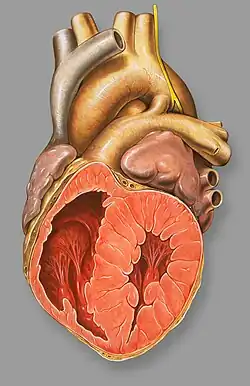

El ductus arterioso persistente o conducto arterioso persistente (CAP) o persistencia del conducto arterioso (PCA) es la persistencia, después de nacer, de la comunicación que habitualmente existe entre el sistema arterial pulmonar y la aorta durante la vida fetal, denominado ductus arteriosus. La causa se desconoce y en el 90 por ciento de los casos se presenta como un defecto único.

Inicialmente no hay cianosis, pero con el tiempo se desarrolla una enfermedad obstructiva de los vasos pulmonares, lo que produce una inversión del flujo sanguíneo y cianosis. El conducto arterioso persistente debe cerrarse a la edad más temprana posible. El tratamiento de elección es el cateterismo terapéutico que consiste en introducir a través de catéter un dispositivo que ocluya el ductus. En algunas circunstancias, como pacientes prematuros puede ser necesaria una intervención quirúrgica.[1]

El conducto arterioso persistente es común en bebés con problemas cardíacos congénitos tales como el síndrome del corazón izquierdo hipoplásico, transposición de los grandes vasos y estenosis pulmonar.